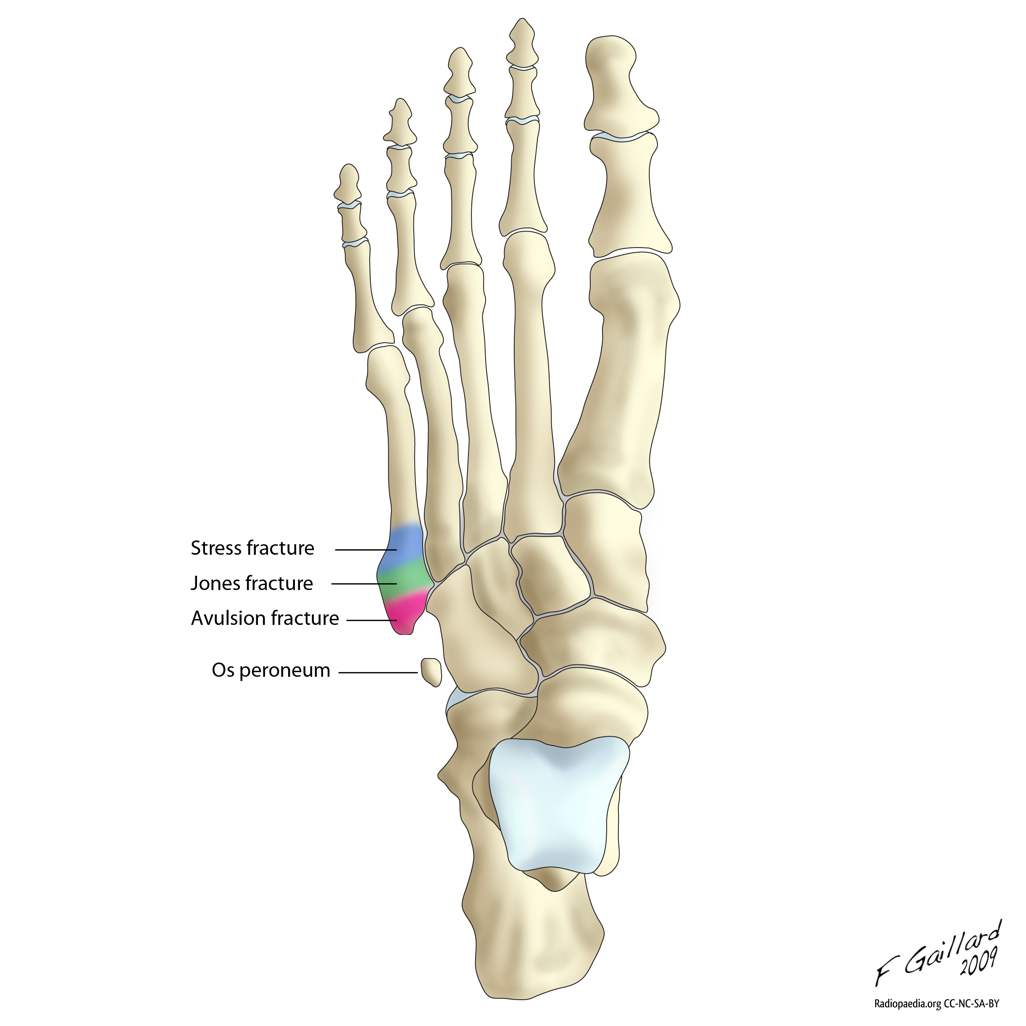

Jones Fracture

Fractures

Avulsion Fracture

• Most common fx of 5th metatarsal

• Avulsion from peroneus brevis muscle

• Lateral cord of plantar aponeurosis could also cause the avulsion

Stress Fracture

Case courtesy of Frank Gaillard, Radiopaedia.org, rID: 7644